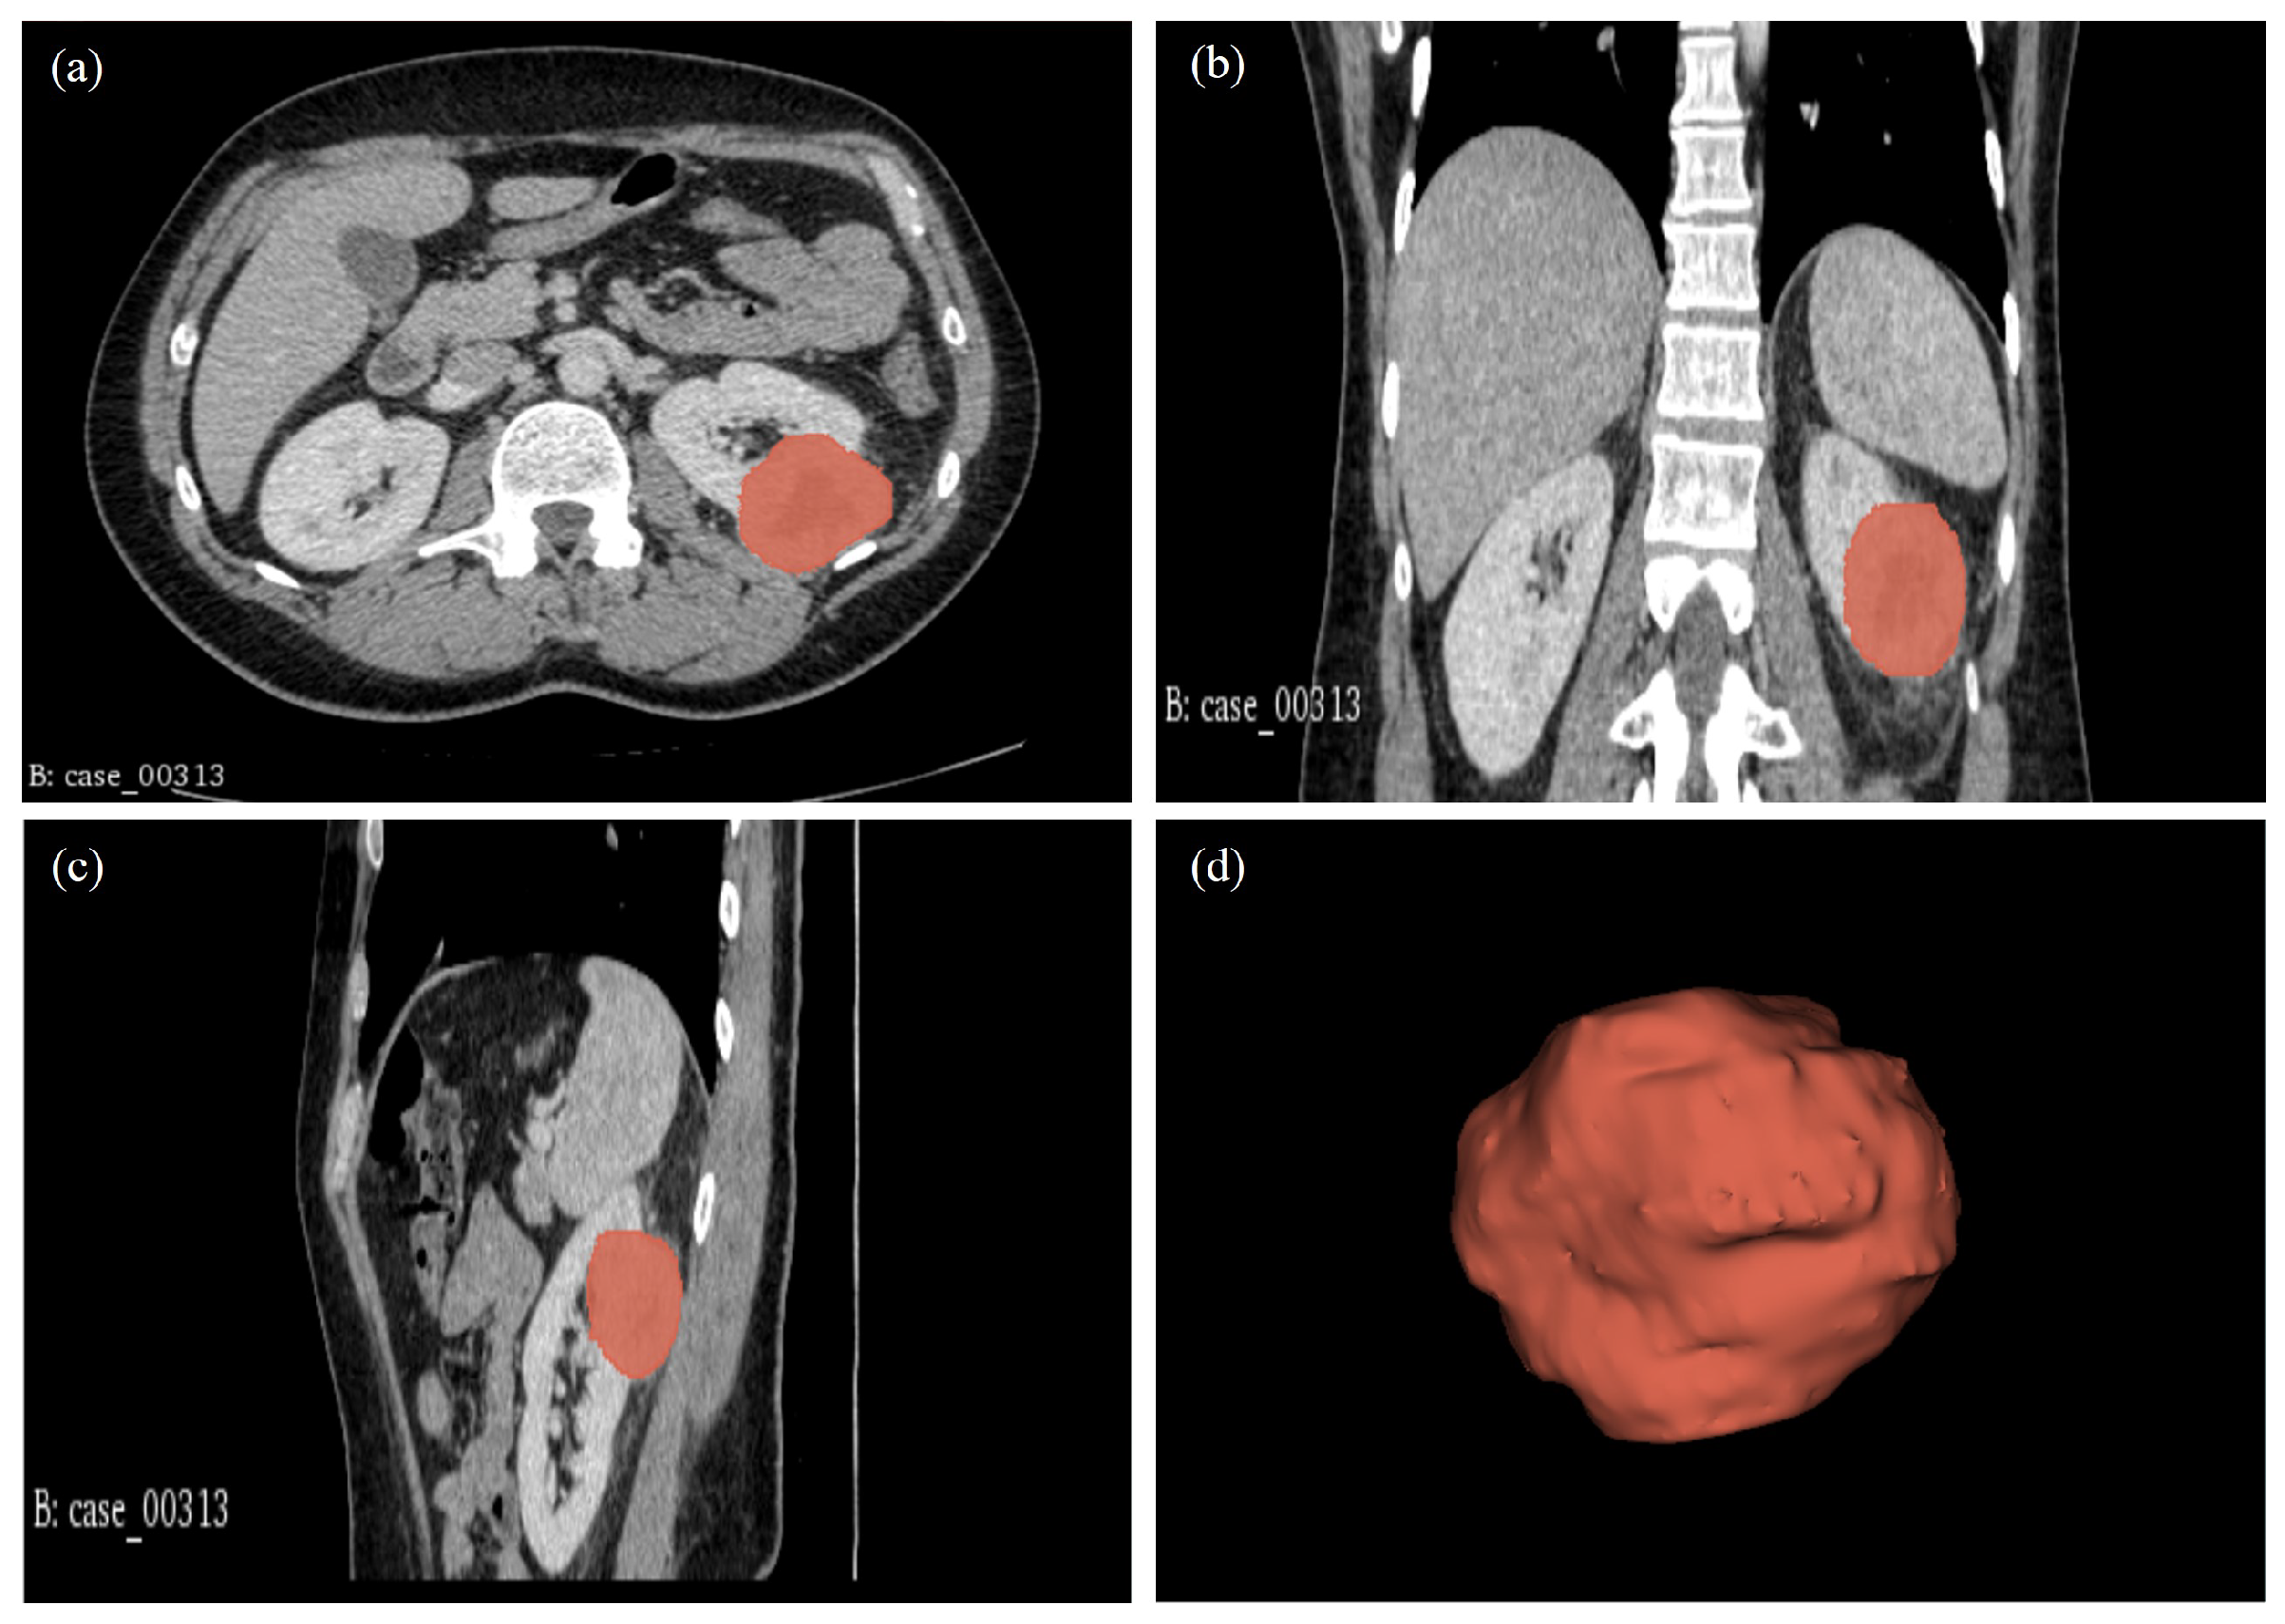

| 00313* | CT: RCC. Highly suspicious of malignancy. Histology: PN; sections show a cellular tumour composed of large nodules of bland cells with abundant eosinophilic cytoplasm and regular nuclei. In areas, smaller islands of similar cells are present with surrounding oedematous stroma. At the periphery of the larger nodules, there are groups of slightly different appearing cells with more hyperchromatic nuclei and less eosinophilic cytoplasm. Central myxoid degeneration/scarring is present. Immunohistochemistry shows that the more eosinophilic tumour cells are negative for vimentin and slightly positive for CD10. There is focal positivity for CK7 but diffuse positivity for CD117. The smaller more hyperchromatic tumour nuclei are positive for vimentin and cytokeratin 7. Despite some unusual morphological and immunohistochemical features, the overall appearance in keeping with the gross appearance of the tumour is best regarded as those of a benign oncocytoma. The tumour appears clear of the sinus excision margin by 2-3 mm. |